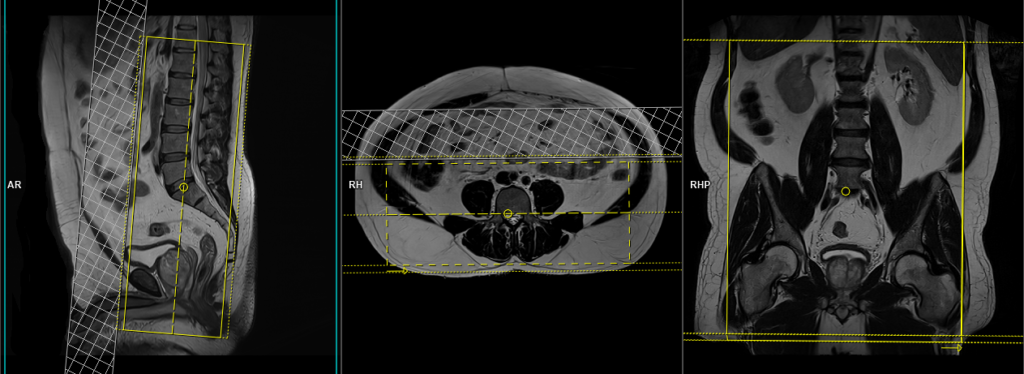

T1 TSE Axial 3mm SFOV

Plan the axial slices on the sagittal plane; angle the planning block perpendicular to the spinal canal. Check the positioning block in the other two planes. An appropriate angle must be given in the coronal plane (perpendicular to the lumbar spines). Slices must be sufficient to cover the lumbosacral plexus from L1 down to the pubic symphysis.

Parameters

TR 400-600 | TE 15-25 | SLICE 3 MM | FLIP 150 | PHASE R>L | MATRIX 384X320 | 250-300 | GAP 10% | NEX(AVRAGE) 2 |